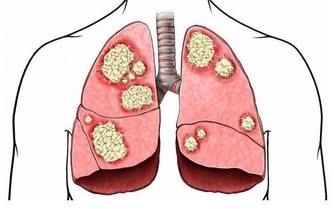

***6 吃飯快,更易患代謝綜合症***

日本廣島大學研究人員耗時5年的一項研究發現,進食速度快的人患代謝綜合徵的比例為11.6%,而進食速度慢的人患這一綜合徵的比例僅為2.3%。